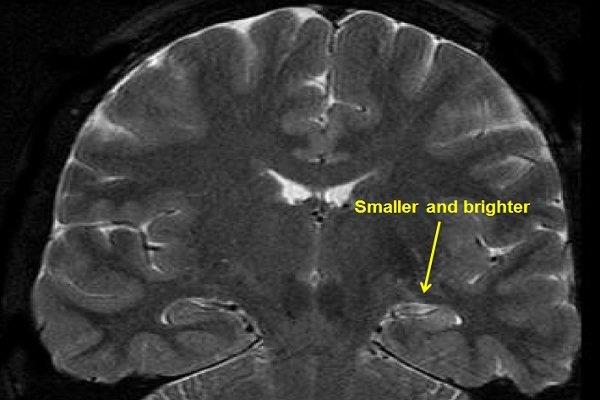

Temporal lobe epilepsy is one of the most common forms of partial epilepsy in adults, according to a study in the journal Imaging Brain Diseases. This condition causes uncontrolled electrical activity in the brain that can lead to seizures.

Temporal lobe epilepsy.